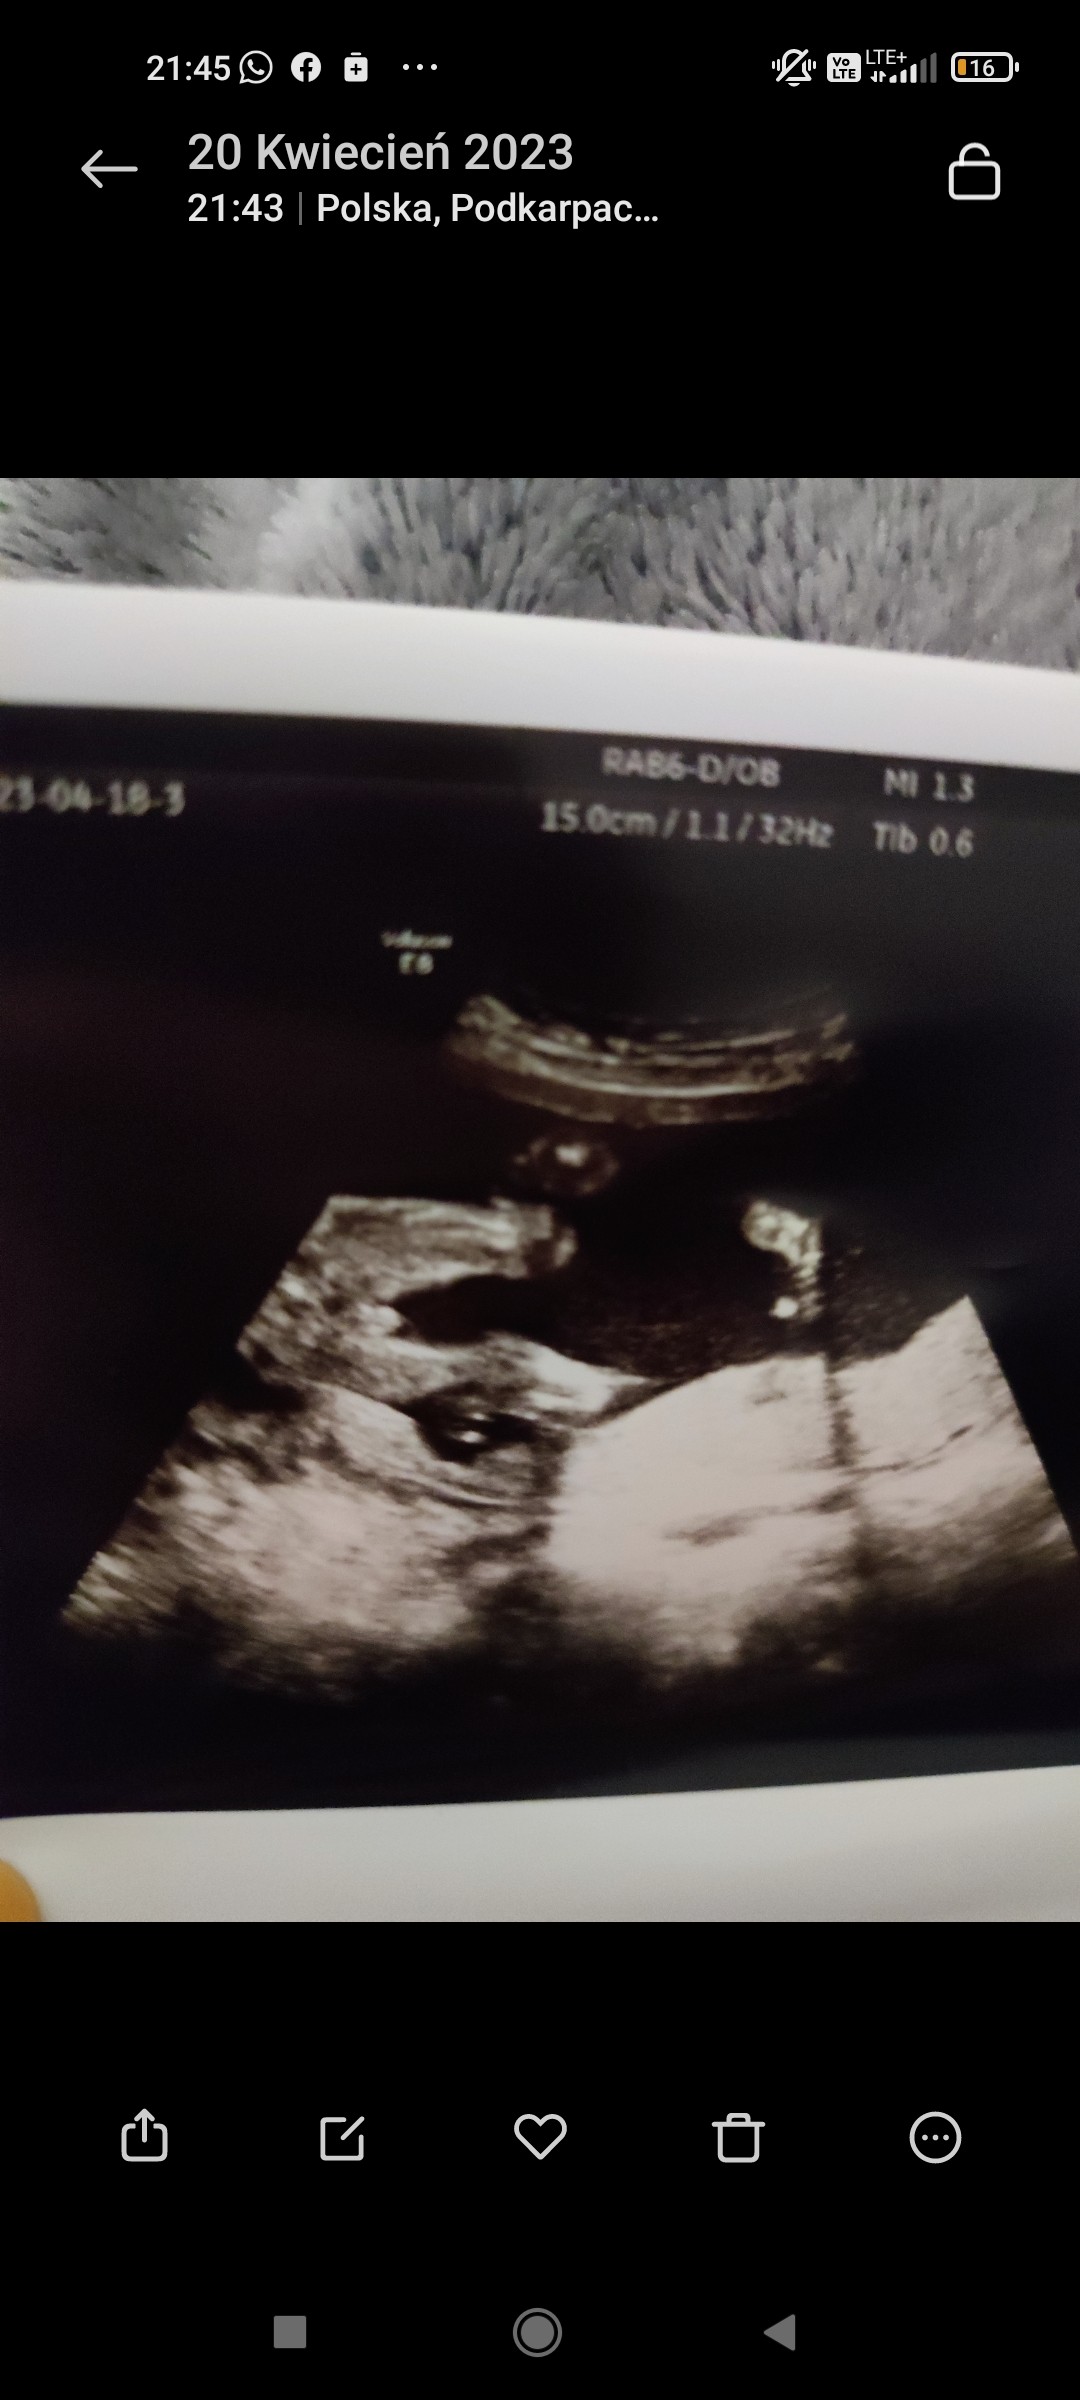

Cześć dziewczyny, powiedzcie czy jest tutaj cień szansy na dziewczynkę? W 12+1 z wyrostka była dziewczynka, w 16 tyg też raczej dziewczynka, a na ostatniej wizycie w 20+1 tyg dostałam takie zdjęcia

czy to może być rączka między nogami lub pępowina? Na tym zdjęciu nie do końca chyba jak chłopiec